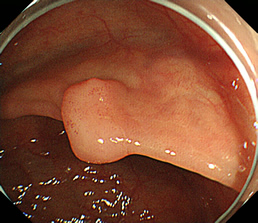

見つかったポリープ

ポリープに色素を吹きかけた状態

粘膜下層に生理食塩水を注入し、盛り上げた状態

高周波電流で粘膜下切除を行った状態

切除後クリップにて止血胃瘻造設術